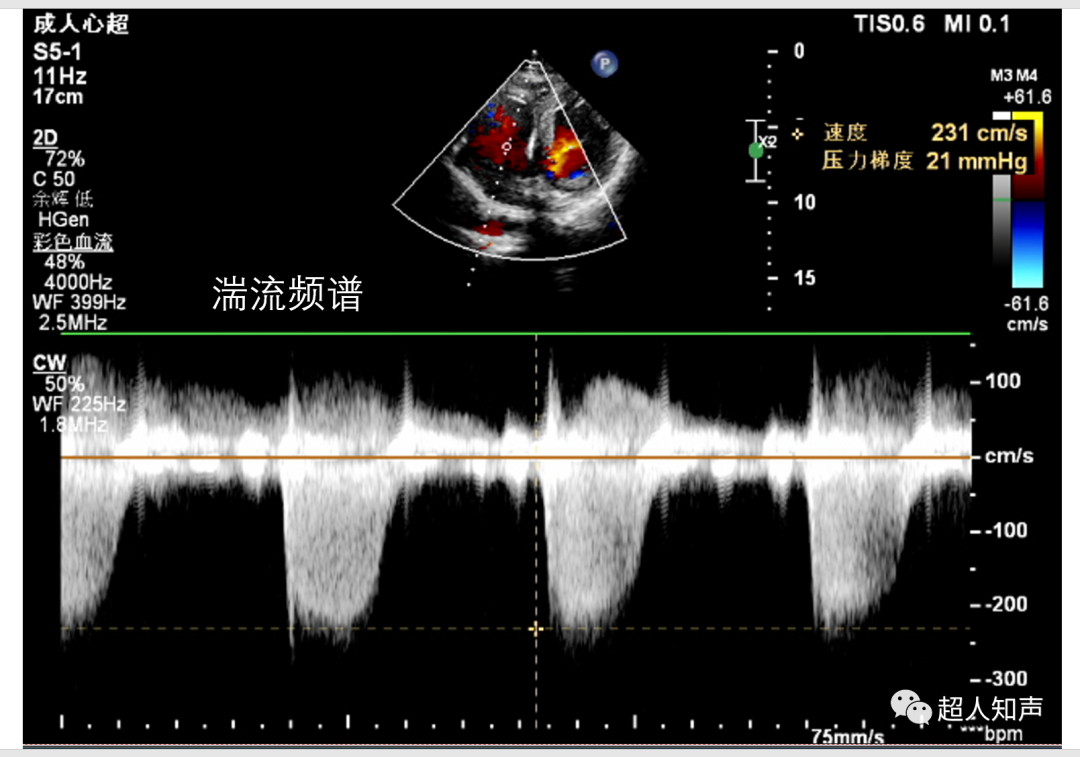

2、湍流 为宽频谱,频谱波形不规整、双向、没有频窗。频谱信号音粗糙、刺耳。

9.测量跨瓣压差。可利用简化伯努利方程△P=4Vmax2计算,△P即压差(PG),Vmax为Vp,单位是m/s。(如下图:PG=4×1.142≈5mmHg)